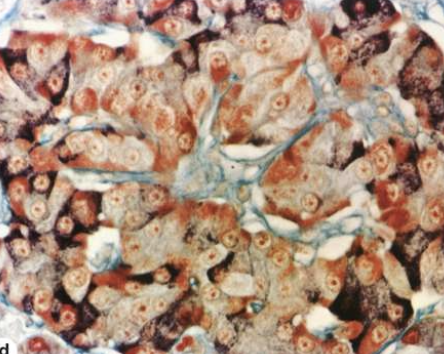

What does the modified aldehyde fuchsin stain reveal about the cells in the Islets of Langerhans?

Peripheral α cells stain deep brownish purple

Central β cells stain brownish orange

Reticulin CT along the islet capsule & capillaries stains green